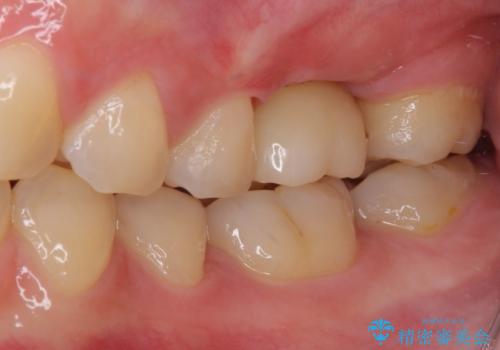

インプラントによる補綴治療とインビザライン矯正

- 抜歯が必要と診断された奥歯を気にして来院された患者様です。

抜歯の上インプラントによる補綴治療を行うこととなりましたが、前歯の叢生も気になるとのことで並行して矯正治療を行うこととしました。

歯列不正は軽微であったので、インビザラインによる矯正治療とし、矯正治療中にインプラント埋入を行う予定としました。

痛みがないので、ボロボロのまま放置していましたが、抜歯後は汚れが溜まりにくくなりスッキリとしたようです。

前歯のデコボコも解消され、ブラッシングが楽になりました。